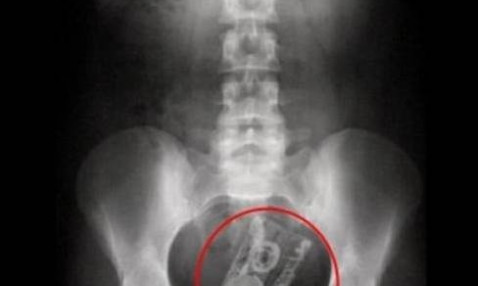

Τα πιο περίεργα αντικείμενα που βρέθηκαν μέσα σε σώματα ασθενών!

Το να είσαι γιατρός σημαίνει ότι πρέπει να είσαι προετοιμασμένος για το απρόοπτο, για το απίθανο, πρέπει να είσαι προετοιμασμένος να αντιμετωπίσεις αυτό που μόνο στις ταινίες του Χόλιγουντ συμβαίνει.

Και όμως κάποτε αυτό το απίθανο που λέμε θα γίνει πραγματικότητα.